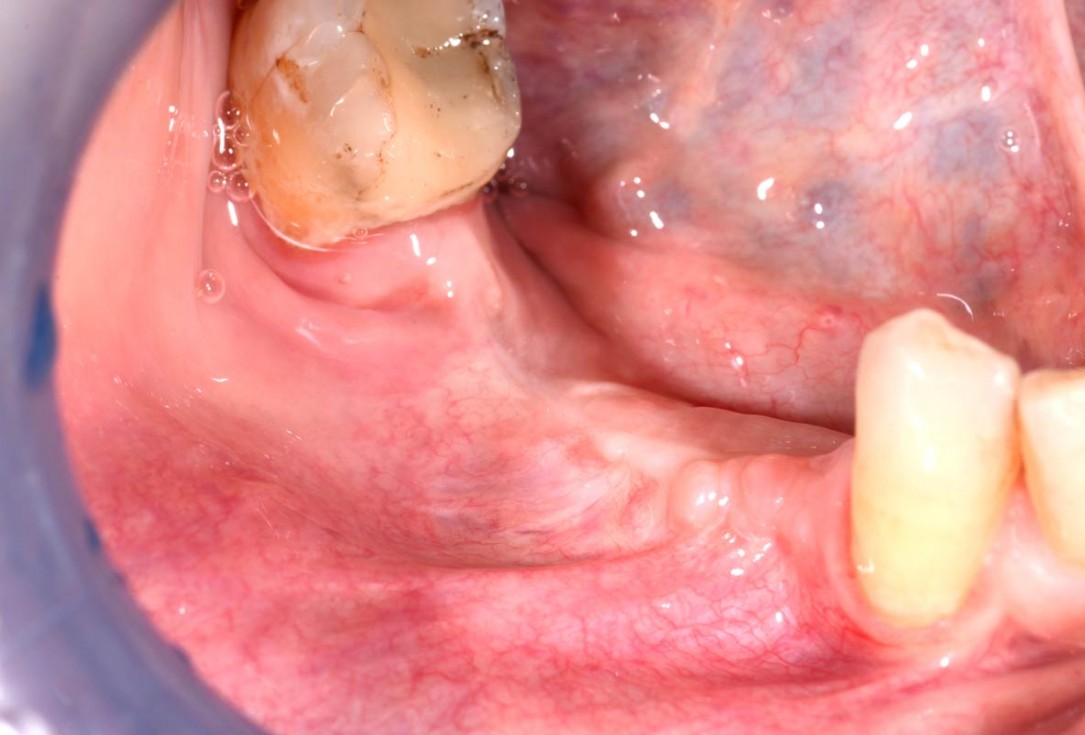

21/29 - Clinical situation 3 months after implantationVertical bone augmentation and broadening of attached gingiva using cerabone®, permamem® and mucoderm® - Dr. R. Naimoli